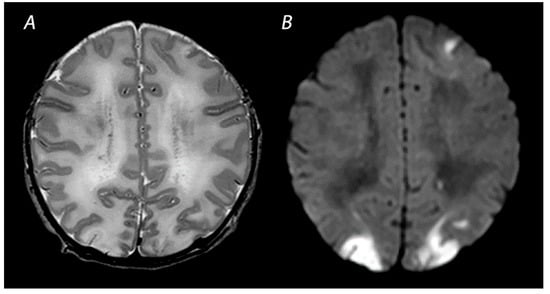

2.3. Near Total Injury